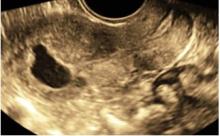

Immagini in 3d di adenocarcinoma endometriale in cui si denota un’infiltrazione del miometrio inferiore al 50% dello spessore miometriale e assenza di coinvolgimento dello stroma del canale cervicale.